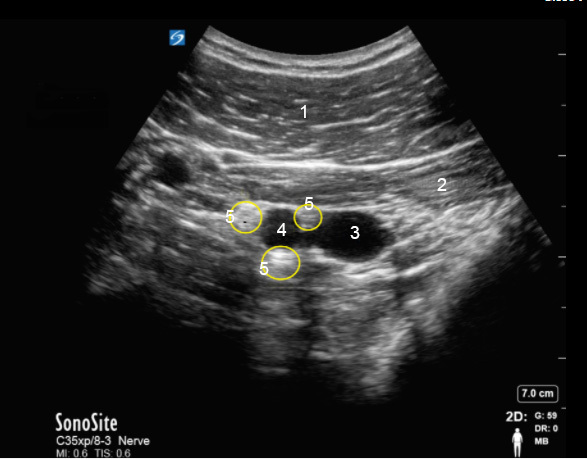

锁骨下神经阻滞 – 注射前图像

胸大肌

胸小肌

静脉

动脉

神经